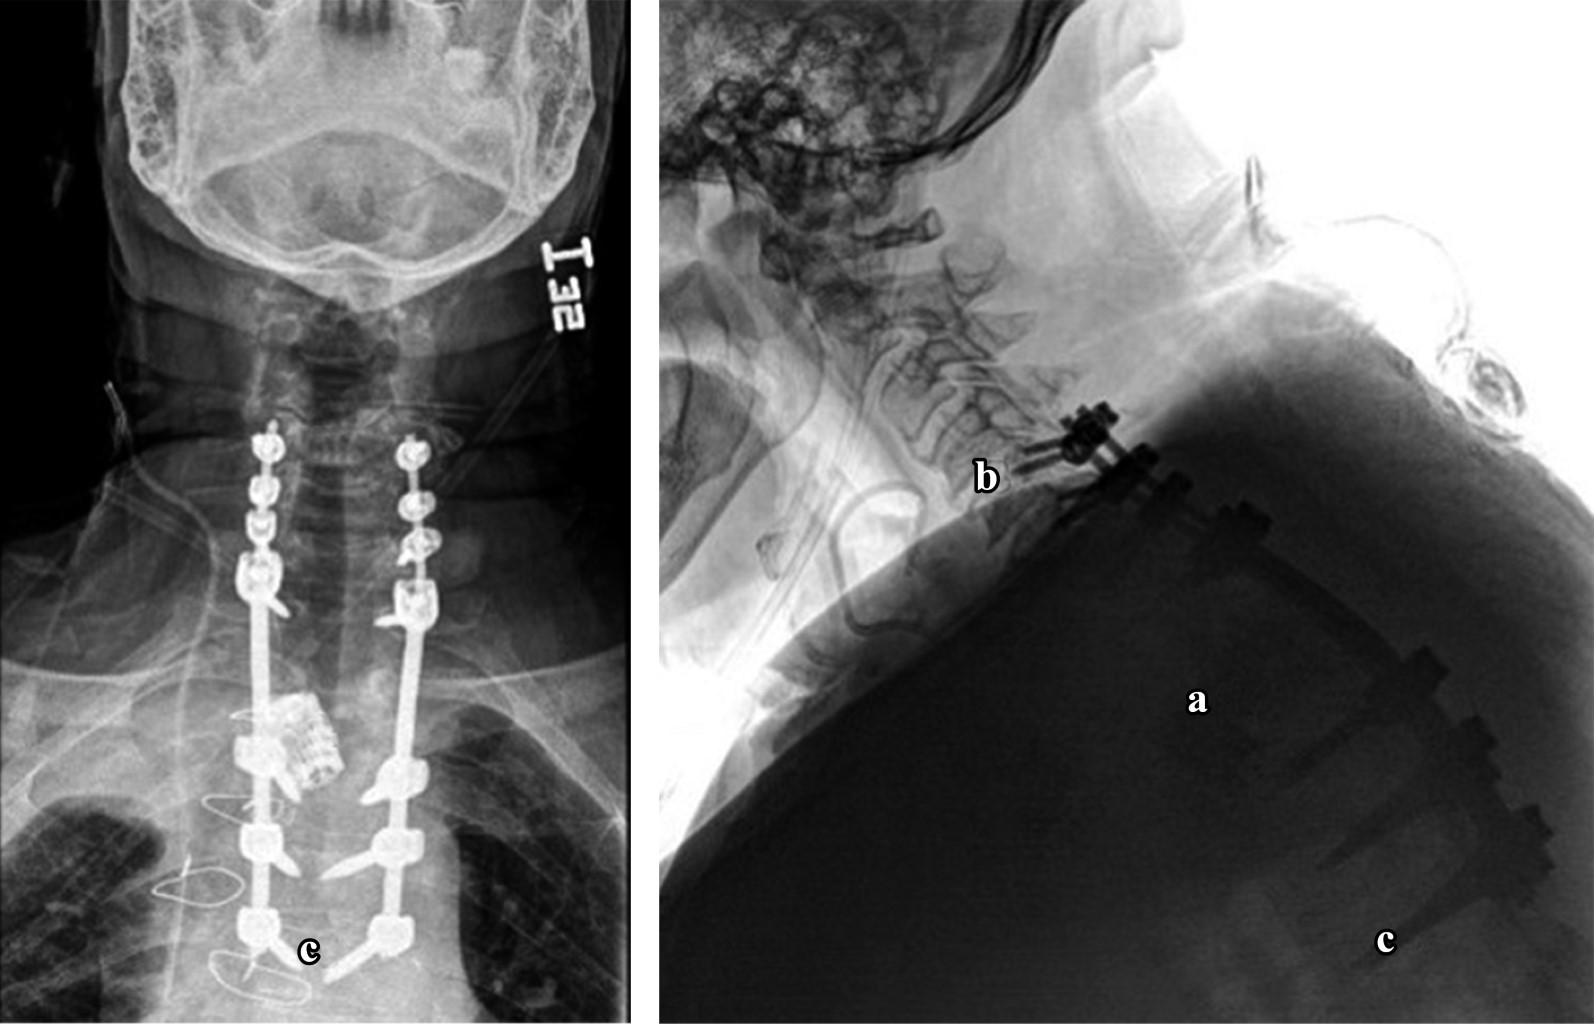

Paciente con espondilodiscitis que presentó deformidad cifótica con compromiso neurológico a nivel torácico superior, quien fue tratado con un nuevo abordaje torácico anterior infraclavicular derecho, como nueva técnica quirúrgica alternativa. Varón de 72 años con deformidad en cifosis secundaria a espondilodiscitis T2-T3 ASIA "C", tratado con instrumentación cervicotorácica posterior C5 a T6 y abordaje anterior transtorácico infraclavicular derecho con colocación de cilindro expandible. Dentro de la revisión bibliográfica realizada en los buscadores no se encontraron técnicas similares a la descrita en este artículo. Dada la complejidad del abordaje quirúrgico, esta nueva técnica se describe como una nueva forma de acceder a la columna torácica superior, demostrando que el abordaje torácico anterior infraclavicular derecho es una nueva alternativa para acceder a la columna torácica superior desde T1 a T4.

Figura 2